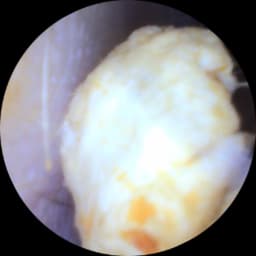

A small camera will assess your membrane health and ear canal. This is a quick painless procedure pictures can be forwarded to your Gp if necessary. Please note we understand if you need to cancel, but a no show you will be charged £25 .Please let us know within 24hrs of your allocated time . PLEASE NOTE THIS IS FREE AND IGNORE IF THE SYSTEM ASKS YOU TO PAY A DEPOSIT!!!I We are trying g to fix this error .